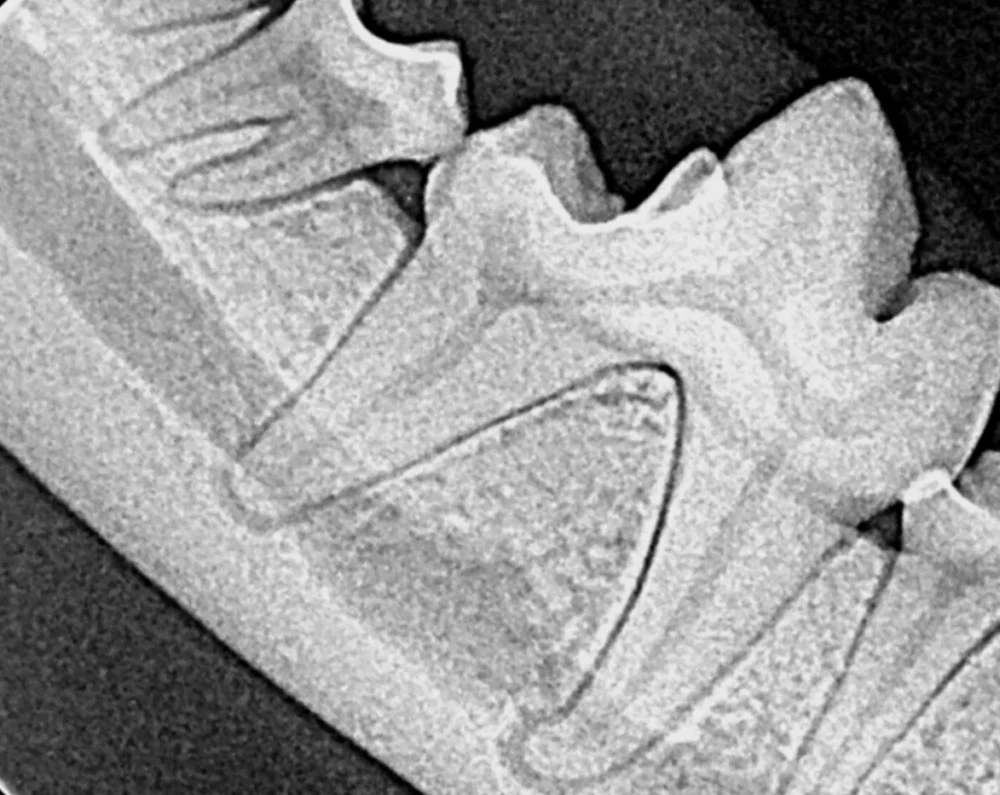

Dental care is an important part of your pet’s overall health. Your pet’s teeth require daily care to prevent the accumulation of plaque and tartar. Complications like periodontal disease and infections in the mouth can spread to other places in the body, like the heart, kidneys, and brain. To stay ahead of dental disease, our hospitals offer comprehensive oral examinations and treatments, complete with digital dental X-rays, in order to make sure no potential problem is overlooked. Our veterinarians also perform oral surgery, such as tooth extraction, when medically appropriate.

Dental disease is the most common condition diagnosed in adult cats and dogs. Symptoms may include bad breath, drooling, difficulty chewing or eating, or pawing at the mouth. Our veterinarians are happy to discuss options for caring for your pet’s teeth. Routine dental care both at Pieper and at home is important to keep your pet healthy and pain free!